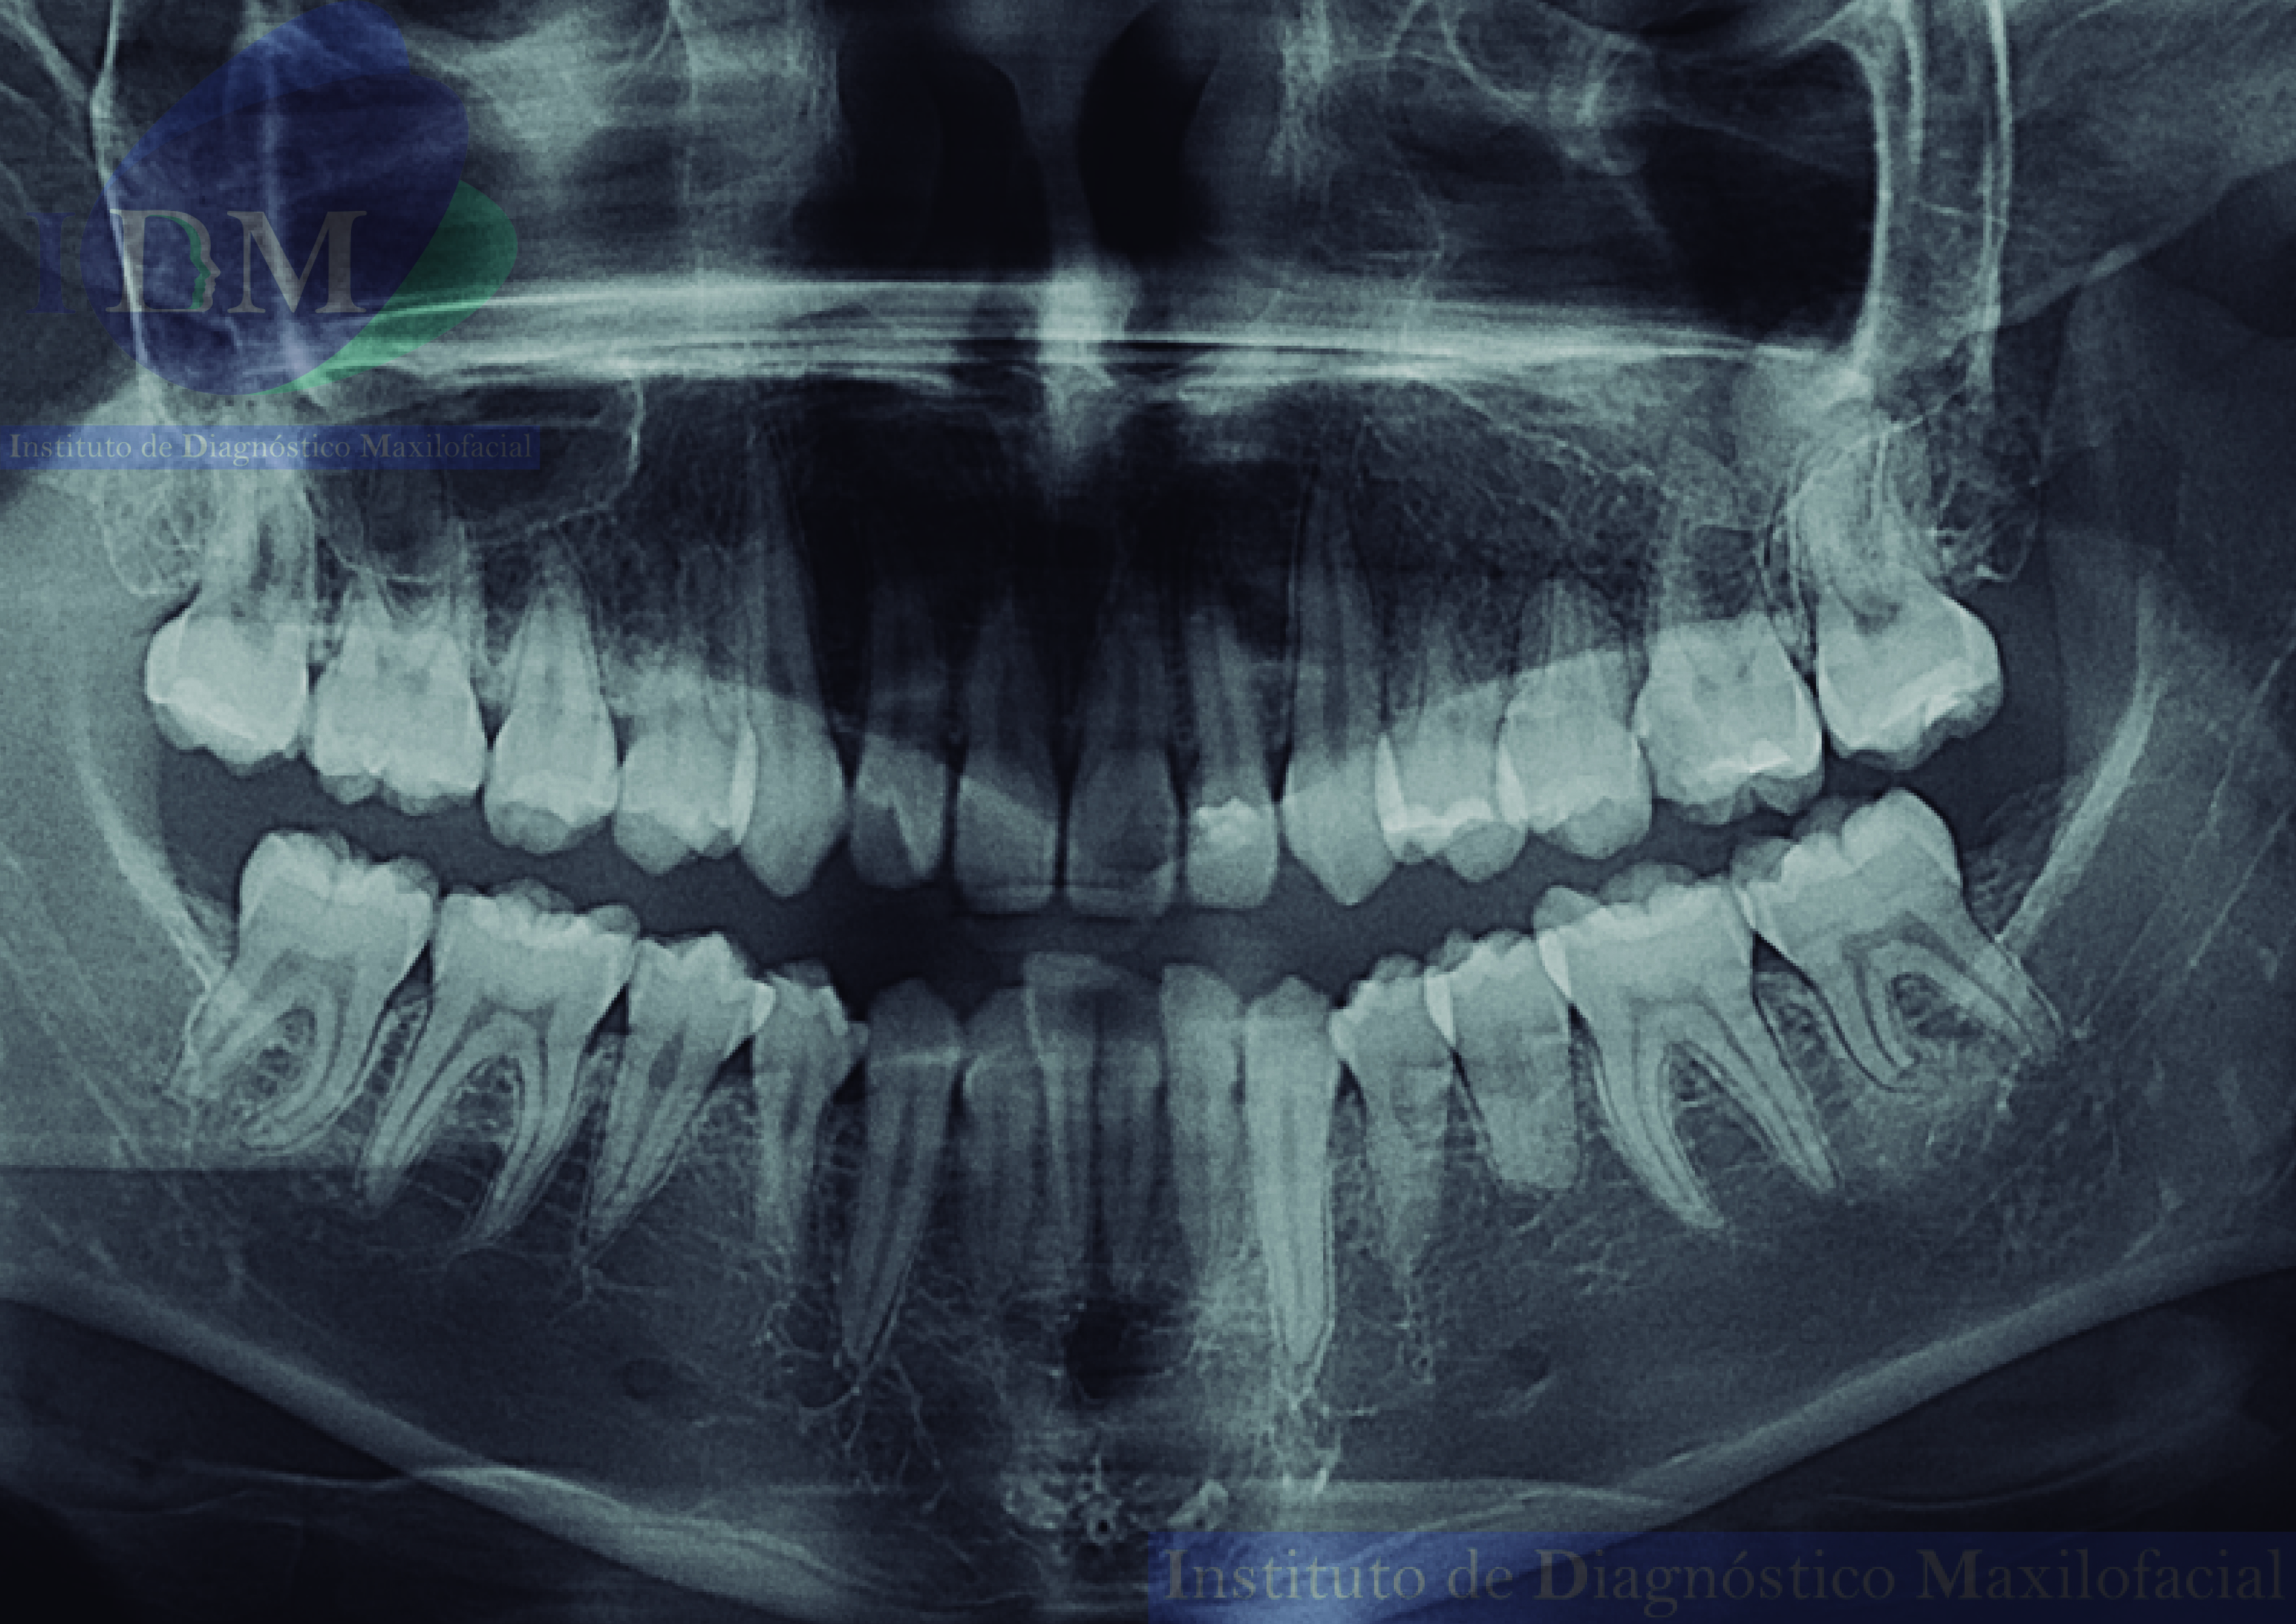

En la radiografía panorámica (Figura 1), se aprecia quiste de retención mucoso en seno maxilar izquierdo y alteración de la morfología coronaria de pieza 12.

Radiografia Panorámica